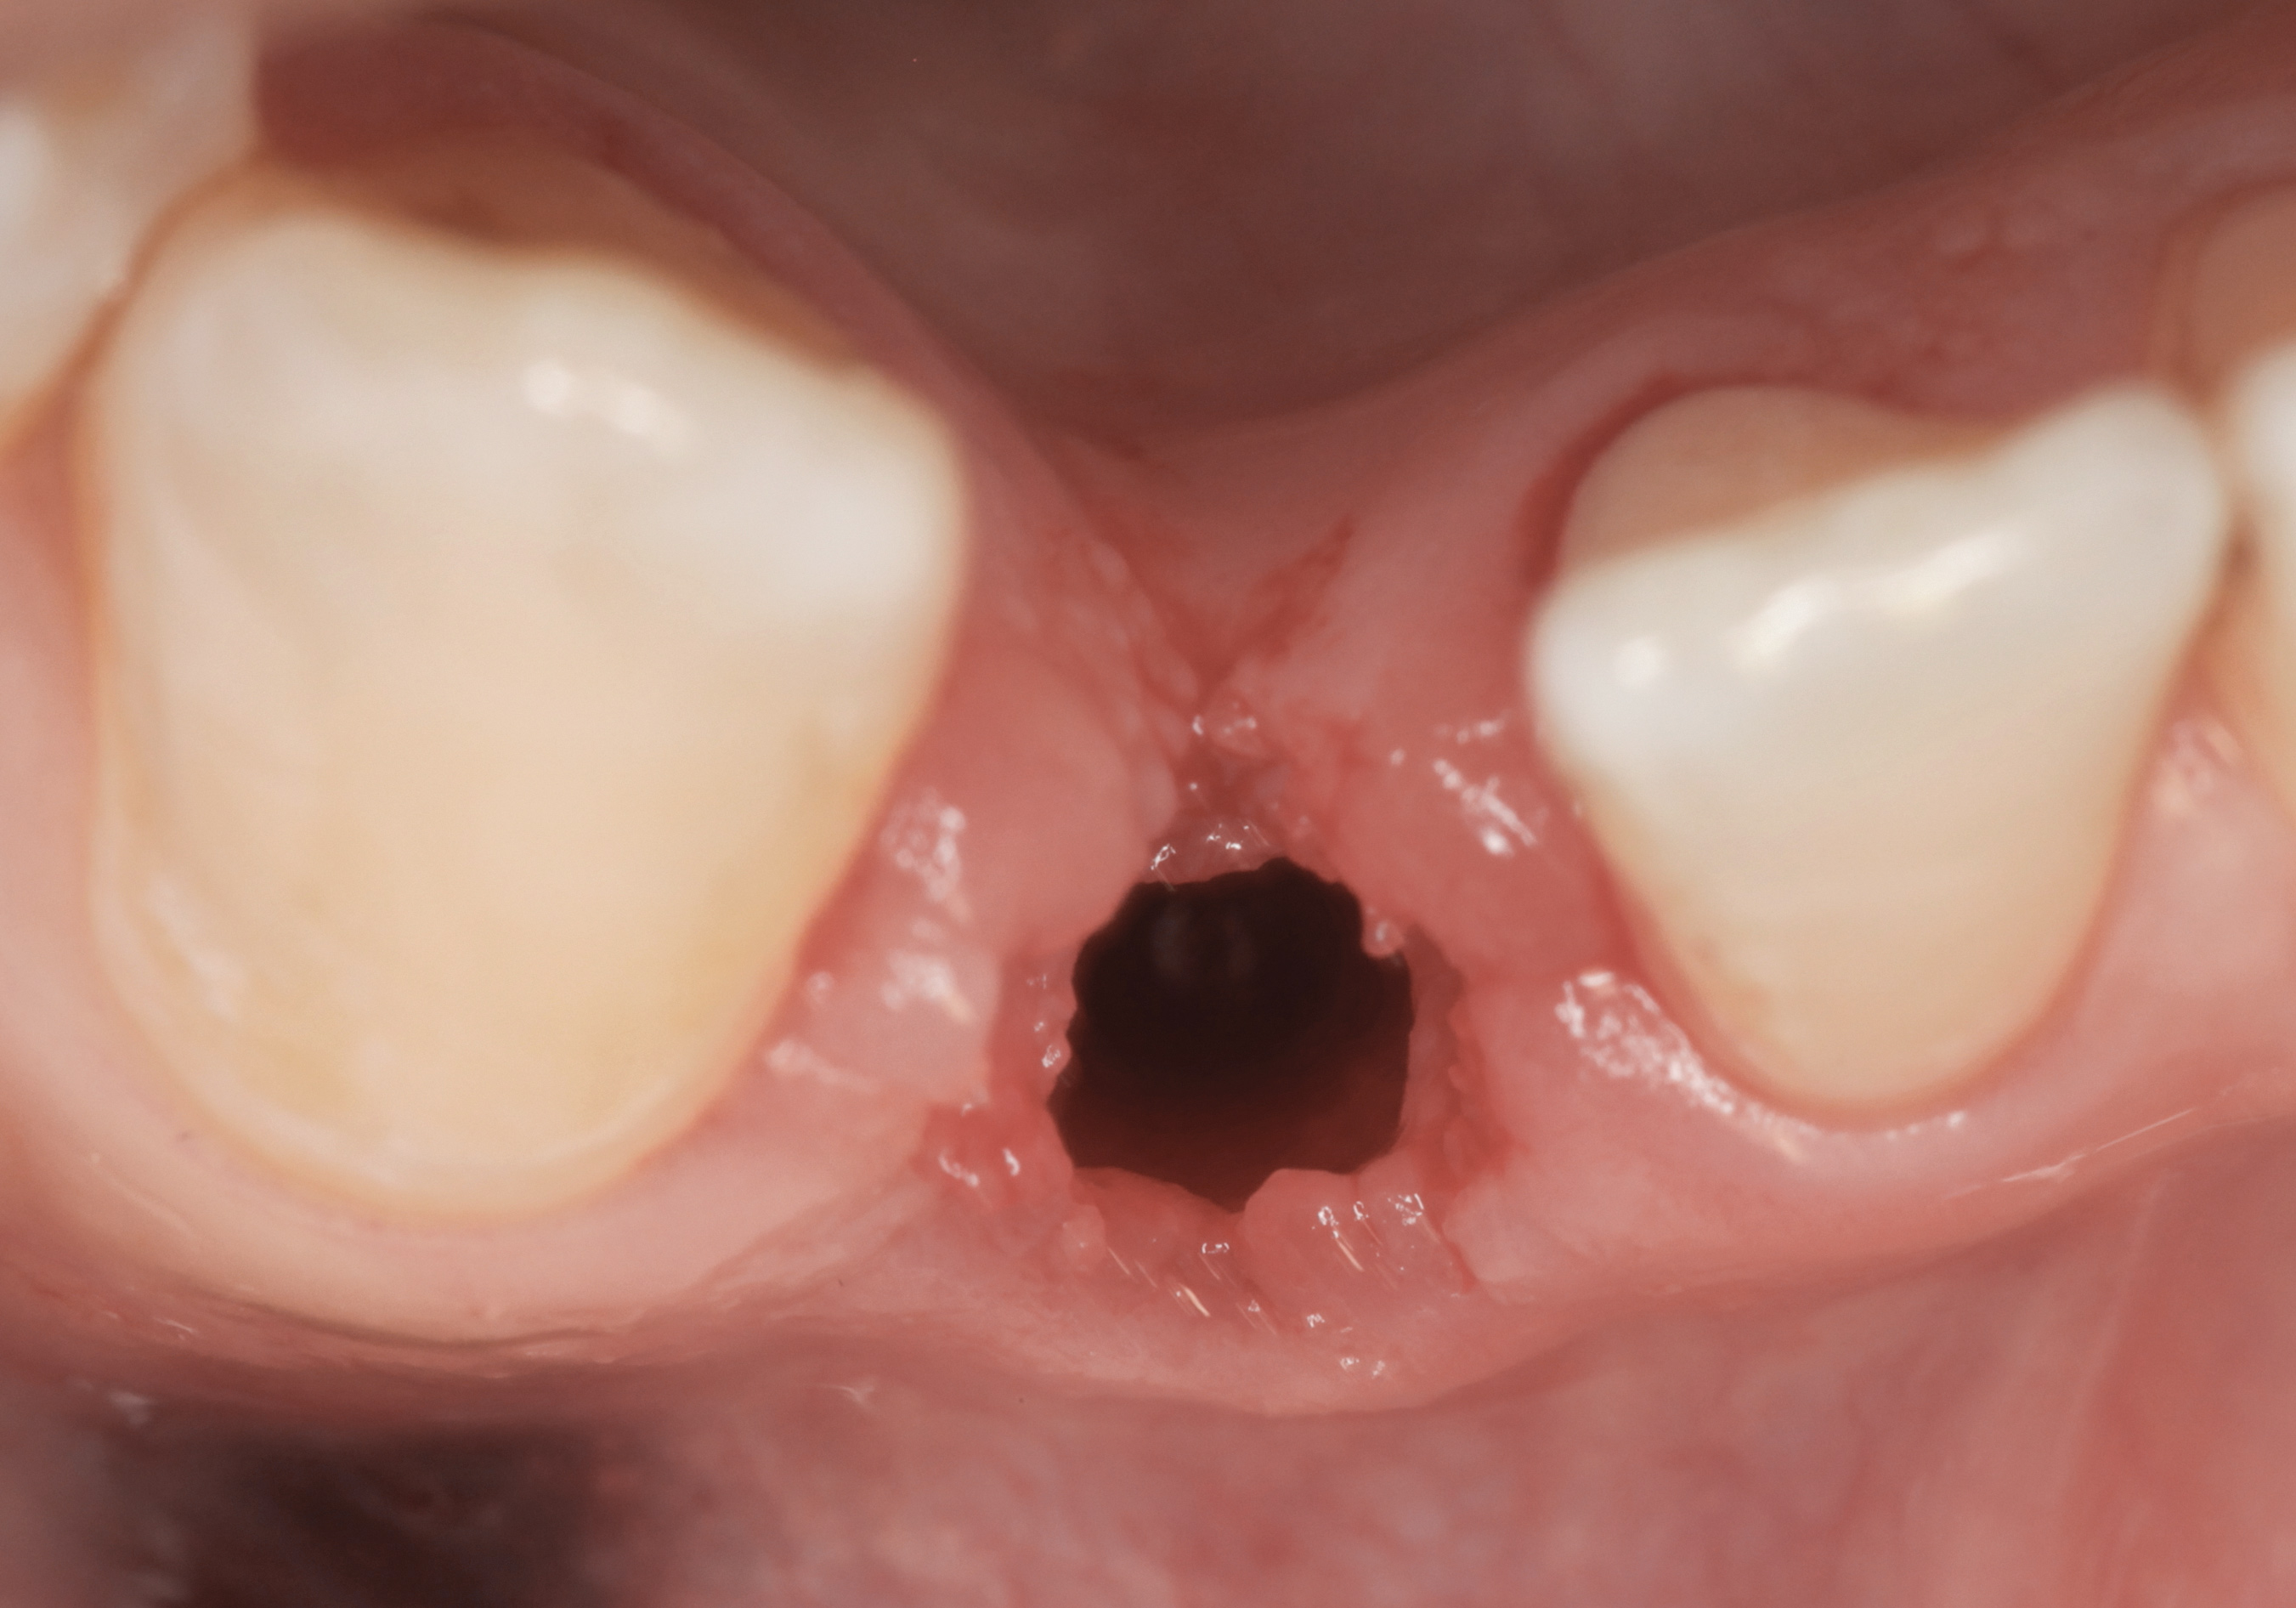

Fig 1. Midfacial recession can affect the esthetics of a smile and lead to an unsatisfactory outcome.

Figure 1

Fig 2. The cause for midfacial recession is excessive labial implant placement. Secondary to poor placement is overcontouring of the implant abutment.

Figure 2

Problem: The implant is placed too facial with significant recession on the midfacial aspect of the abutment and/or crown; the implant is healthy and the patient has a high smile line with an intermediate to thick periodontal phenotype (Figure 1 and Figure 2).17-19